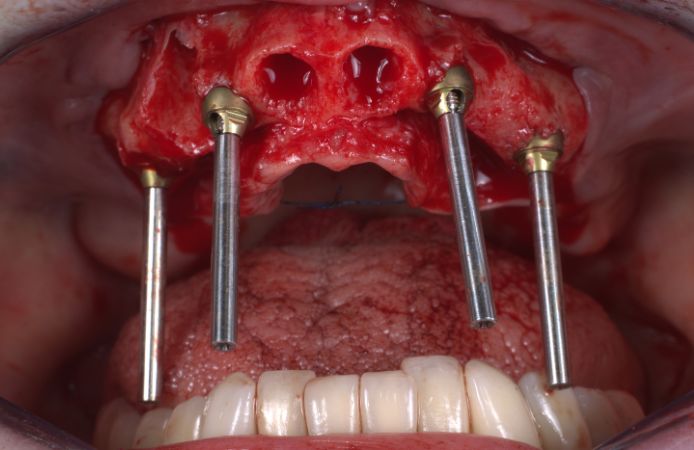

Figure 5.

Four Neoss ProActive Edge implants were immediately installed. The anterior implants were 4.0 x 15 mm.

Figure 6.

The two posterior implants (4.5 x 15 mm) were tilted to maximize the distance between the implants, to avoid the sinus, to maximize the contact with available bone, and to increase stability.

Figure 7.

Occlusal view of the placed implants